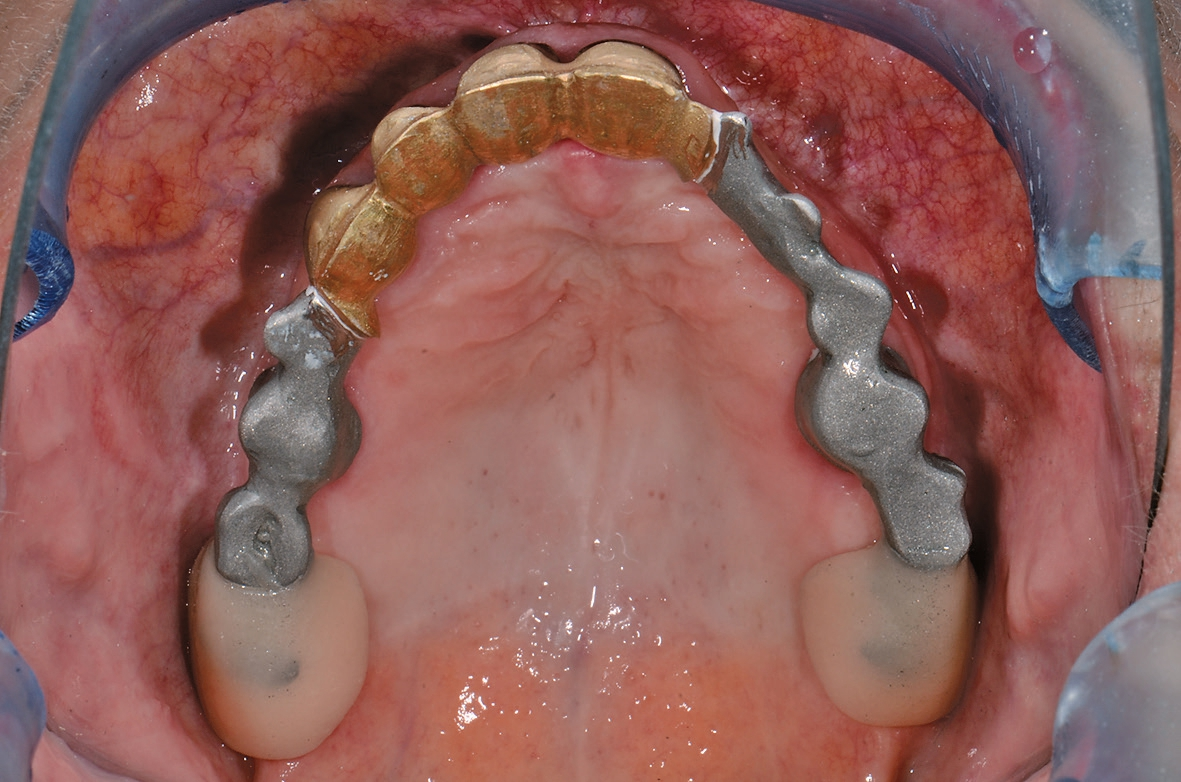

Die seinerzeit 68-jährige Patientin stellte sich im Jahr 2015 in der Klinik für Rekonstruktive Zahnmedizin und Myoarthropathien an den Universitätskliniken für Zahnmedizin in Basel vor, mit dem Wunsch nach einer langfristig stabilen Versorgung im Oberkiefer. Sie war im Oberkiefer mit einer bereits mehrfach angepassten alio loco hergestellten Teilprothese versorgt. Die medizinische Anamnese war unauffällig. Die Mundhygiene der Patientin war bereits zu dem Zeitpunkt auf einem guten Niveau und die parodontale Situation war abgesehen von lokalisiert leicht erhöhten Sondierungstiefen um den längsfrakturierten Zahn 22 sowie beim Implantat in regio 35 stabil. Neben den verblockten Kronen 13-12-11-21 wurde auch die gemischt zahn- und implantatgetragene Brücke 34-35i-36i-x aufgrund mangelhafter Passgenauigkeit als erneuerungsbedürftig eingestuft. Die definitive Neuversorgung im Unterkiefer sollte jedoch auf Wunsch der Patientin bis zum Abschluss der Versorgung im Oberkiefer aufgeschoben werden. Die über 20-jährige Brücke 34-x-36 konnte hingegen sowohl klinisch als auch radiologisch als suffizient eingestuft werden (Abb. 1 u. 2).

In einem nächsten Schritt wurden die Primärteile provisorisch fixiert und zusammen mit den Implantaten und den Schleimhautarealen überabgeformt (ImpregumTM, 3M) zur Herstellung des Meistermodells (Abb. 15). Die Position der Implantate wurde mittels „Verification Stent“ rückkontrolliert und die vertikale und horizontale Kieferrelation intraoral mittels Handbissnahme verschlüsselt. Aufgrund der nicht unerheblichen Achsendivergenz zwischen den Implantaten und den natürlichen Pfeilerzähnen wurde entschieden, die Implantate anstelle von konfektionierten Einzelelementen mit individuellen CAD/CAM-Teleskopkronen (Atlantis Abutments, Dentsply Sirona, Wals bei Salzburg, Österreich) zu versorgen. Konfektionierte Einzelelemente wären durch die Achsendivergenz einem erhöhten Verschleiß unterzogen gewesen, was wiederum mit einem gesteigerten Nachsorgebedarf verbunden gewesen wäre. Nach mehreren Set-up-Einproben konnte schließlich auch das Sekundärgerüst hergestellt werden. Sämtliche Sekundärteile wurden dabei als Vollgussteile designt und mit dem Modellgussgerüst verklebt, mit Ausnahme der Sekundärteile für die Implantatteleskopkronen, welche zur Sicherstellung der Passivität intraoral verklebt werden sollten (Abb. 16 u. 17). Sowohl Primär- als auch Sekundärteile wurden für eine höhere Härte während 30 min bei 400°C vergütet. Anschließend konnte das geschlüsselte Set-up und auf das Gerüst aufgepasst werden. Um die Pfeilerzähne wurde die Prothese offen gestaltet, um eine natürliche Umspülung der Pfeilerzähne zu ermöglichen. Auf ein Palatinalband konnte aufgrund der guten Kammverhältnisse und des breiten Unterstützungspolygons verzichtet werden. Nach einer letzten klinischen Einprobe konnte die Prothese durch den Zahntechniker individualisiert und fertiggestellt werden (Abb. 18).

Die Teleskopkronen und die Wurzelstiftkappe wurden mit Glasionomerzement (KetacTM Cem, 3M) sukzessive einzeln eingesetzt. Die Implantatteleskopkronen wurden mit einem Anzugsdrehmoment von 35 Ncm festgeschraubt und mit weißer Guttapercha und Glasionomerzement (KetacTM Bond, 3M) verschlossen. Nach einer Tragedauer von einer Woche, in der sich die Prothese einlagern konnte, wurden die Sekundärteile der Implantatteleskopkronen und die Matrize der Wurzelstiftkappe intraoral verklebt (Super-T, American Consolidated Manufacturing, Conshohocken, USA) (Abb. 19).